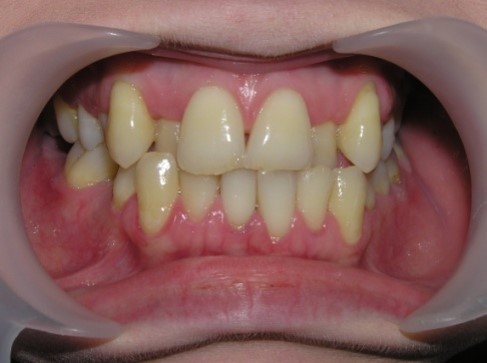

Palatal position of teeth is

characterized by the eruption of one tooth or a group of teeth outside the

dental arc on the palatal side. So, most often, incisors or second premolars

eruption.

The frequency of palatal position of

teeth according to the Department of Orthodontics: central incisors - 11.35%,

central and lateral incisors of one side - 15%, groups of central and one

lateral incisor - 12.3%, the most common palatal position of lateral incisors

(one or both) - 61.35%. In 57% of children, there are erased areas on the

incisal and vestibular surfaces of palatal-displaced teeth as a result of the

functional action of antagonist teeth. With a slight overlap, abrasion of the

cutting edge and shortening of the abnormally located tooth are observed. In the

palatal location of the upper jaw incisors, flattening of the frontal area of

the upper jaw and lengthening of the frontal area of the lower jaw are

determined. In this case, exposure of the necks of the lower frontal teeth,

violation of their stability and inflammation of the gums may be observed, and

the clinic of catarrhal or atrophic gingivitis develops as a result of

functional trauma.